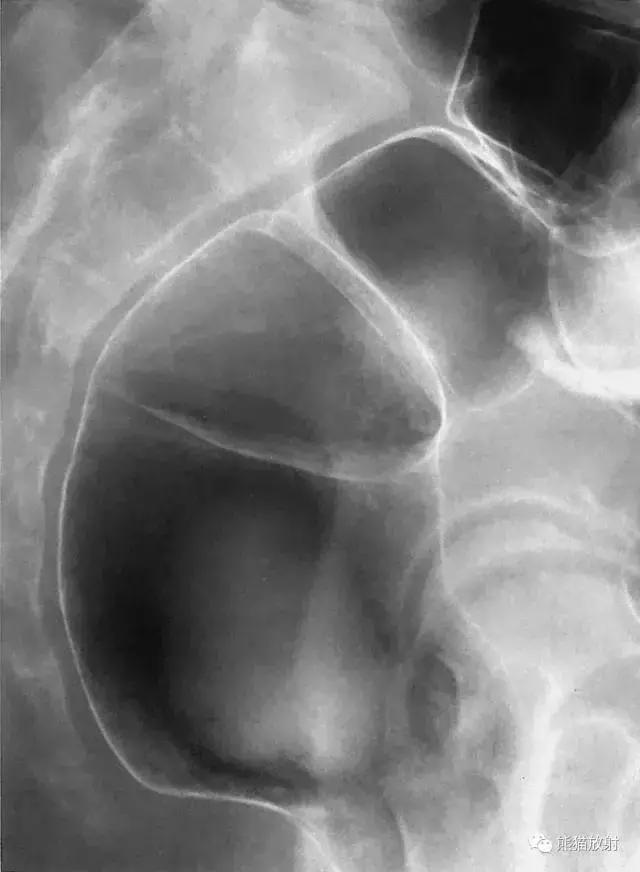

九、回盲部(点片)

图17 回盲部(点片)

图18 回盲部解剖示意图。1 结肠袋,2 升结肠,3 回肠,4 回盲瓣,5 末端回肠,6 盲肠